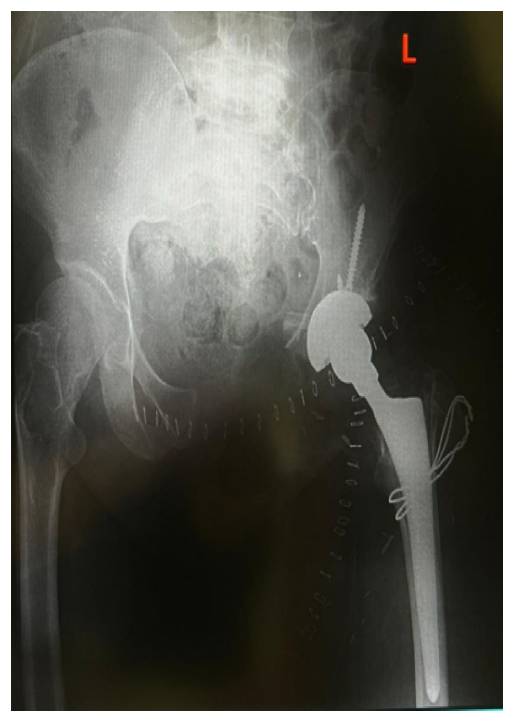

Post-Surgery: The X-ray shows a total hip reconstruction after resection.